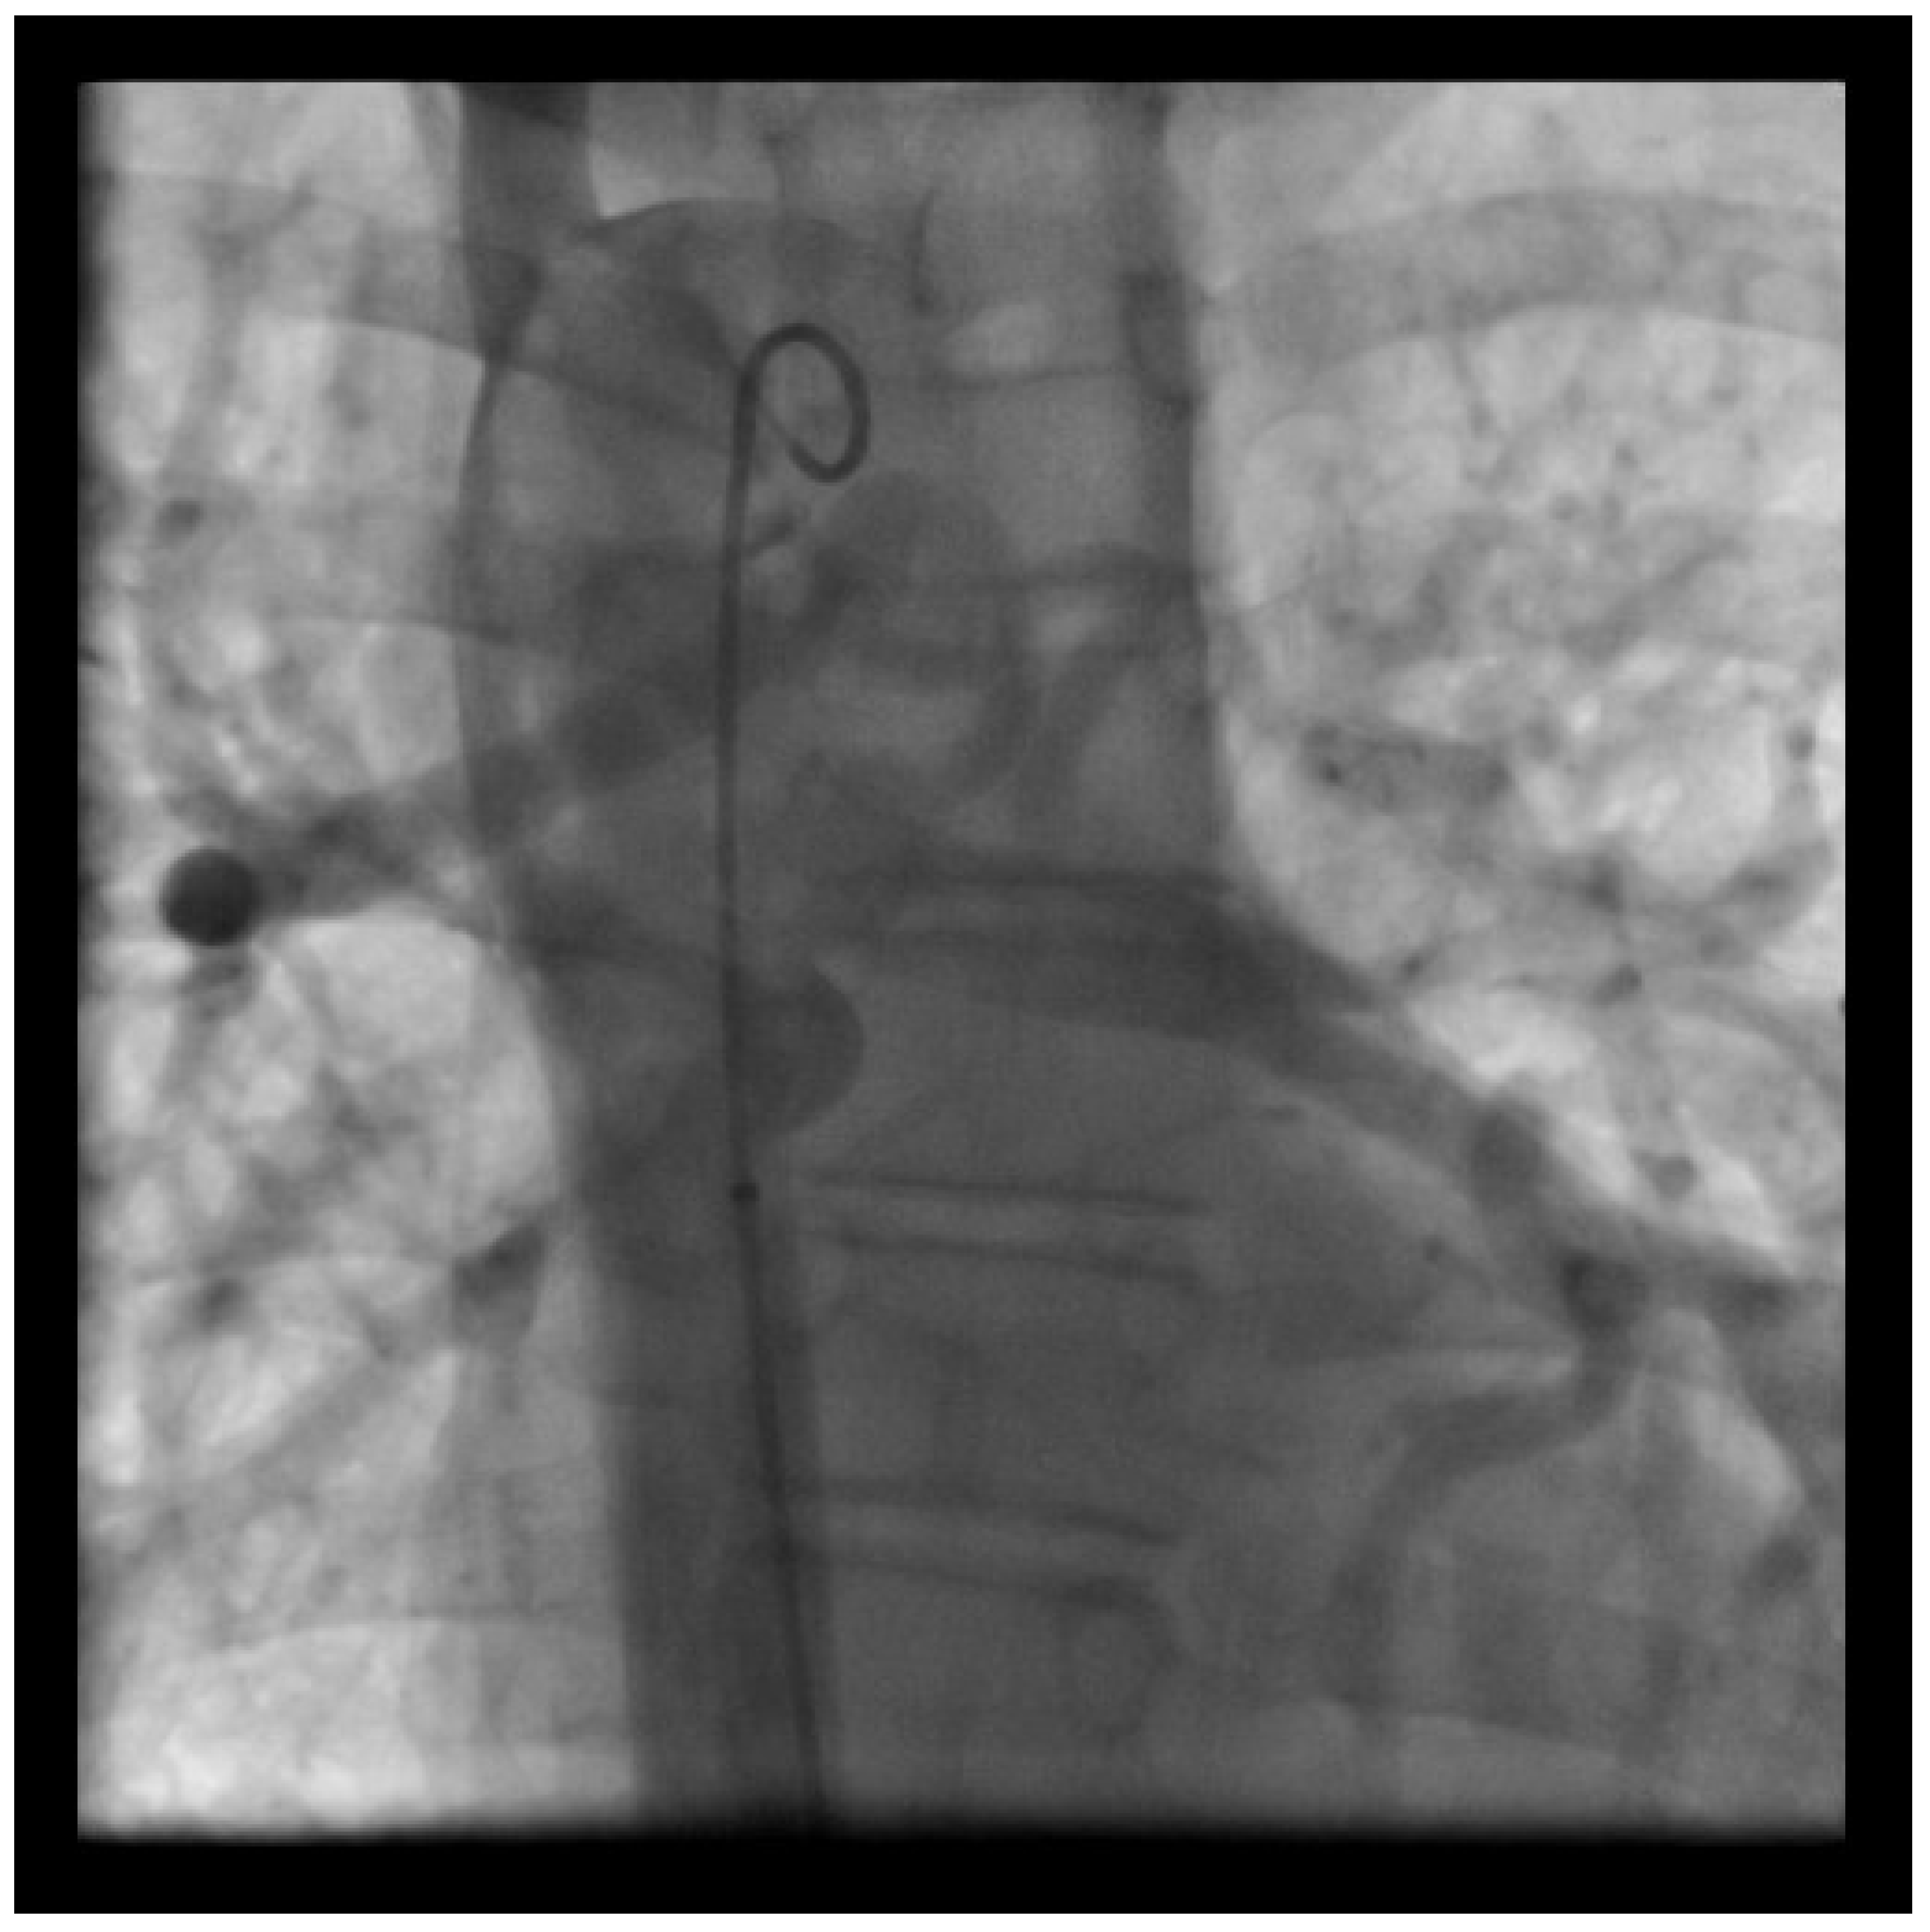

Chronic Thromboembolic Pulmonary Hypertension

- Verbelen, T.; Cools, B.; Fejzic, Z.; Eynde, R.V.D.; Maleux, G.; Delcroix, M.; Meyns, B. Pulmonary endarterectomy in a 12-year-old boy with multiple comorbidities. Pulm. Circ. 2019, 9. [Google Scholar] [CrossRef] [PubMed] [Green Version]